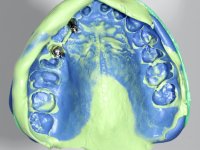

A temporary acrylic bridge made in the laboratory with 7 elements was made, with teeth 11,21, 25 and 26 as pillars. The old bridge was removed and tooth 24 was extracted. The provisional bridge after relining was cemented in the mouth. Two implants were placed in the teeth 22 and 24 and 3 months after this intervention an impression was made to make a temporary bridge screwed over the implants and cemented to the teeth. The bridge was placed in the mouth and teeth 25 and 26 were extracted. 3 months later, surgery was performed to fill the maxillary sinus and 6 months later the implant was placed in the location of tooth 26. After osseointegration of this implant, the final impression was made for the final work. The bridge over the implants was permanently screwed on and the bridge over the teeth was cemented with resin-reinforced glass ionomer cement.